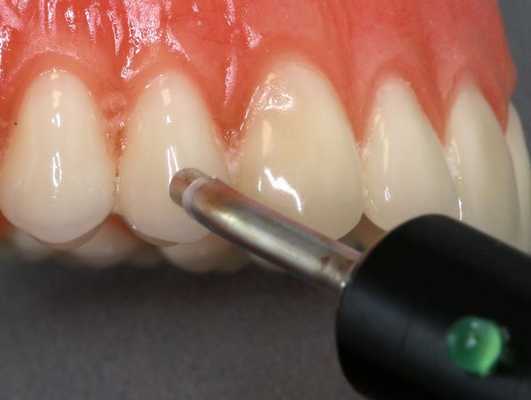

Диагностика периодонтита проводится на основании жалоб пациента, анамнеза заболевания, оценки общесоматического статуса, осмотра головы и шеи, полости рта, зуба, его перкуссии, зондирования и термопробы, электроодонтодиагностики (ЭОМ) и рентгенологического исследования. [10]

ЭОМ — это метод стоматологического исследования, основанный на определении порогового возбуждения болевых и тактильных рецепторов пульпы зуба при прохождении через неё электрического тока.

Методика лечения перикоронарита с помощью лазерной терапии позволяет воздействовать инфракрасным лучом непосредственно через кожу. Инфракрасное лазерное излучение низкой интенсивности проникает глубоко под кожу и оказывает противовоспалительное и противоотечное действие, так же стимулируется обмен веществ и приток крови к пораженному участку. Лазерное излучение кроме прочего обладает достаточным обезболивающим эффектом, чтобы купировать болевой синдром при перикоронарите. Лазерная терапия длится 7-10 дней, противопоказанием является наличие онкологических процессов в полости рта.

В качестве лечения перикоронита зуба мудрости может использоваться и лазерная терапия. Ее смысл заключается в воздействии на поврежденный участок лучом инфракрасного цвета, выраженного противовоспалительного, обезболивающего и бактериостатического действий. Луч стимулирует приток крови и, соответственно, ускоряет процесс регенерации тканей. Лазерную терапию пациенту назначают ежедневно, в течение 7-10 дней.